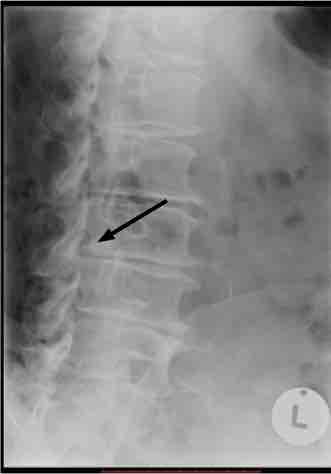

Notice the retrolysthesis of L3 on L4. There is marked disc degeneration, and the vertebra has subluxated posteriorly; it's circled.

Notice too the extreme facet degeneration at L5-S1 (circled).

See the nasty little dagger protruding into the IVF from the body of L3? It's arrowed below.